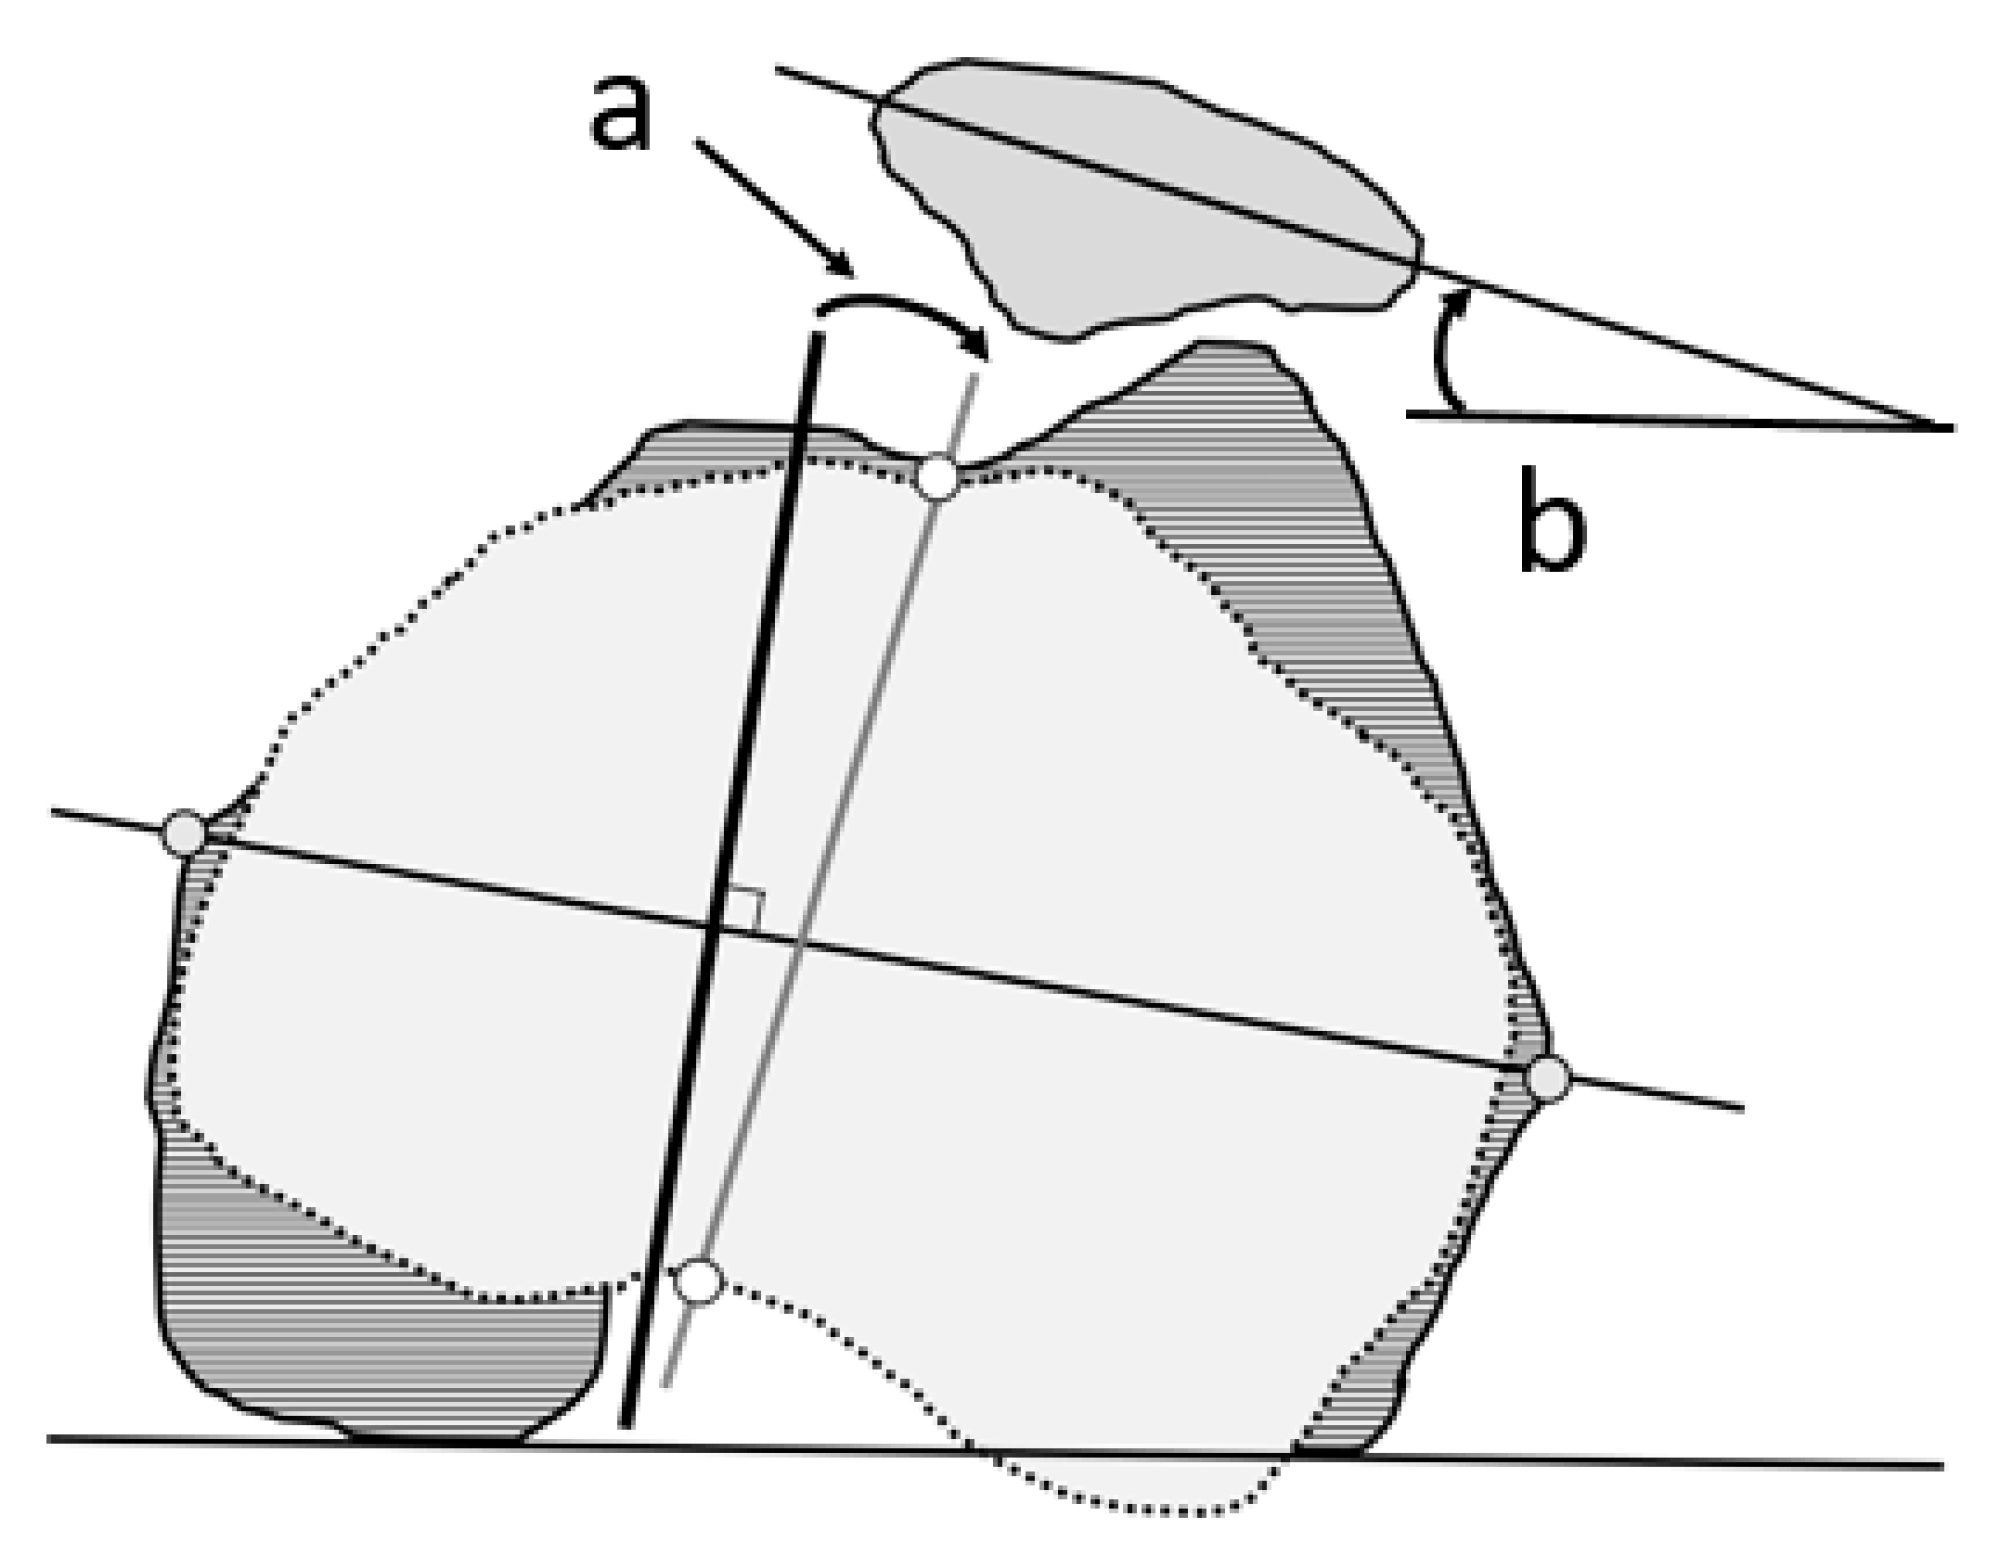

2.3. Measurement